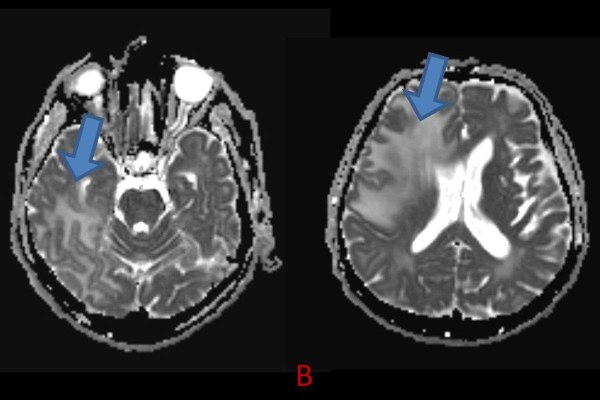

- B) ADC haritasında kolaylaşmış difüzyon (mavi ok).